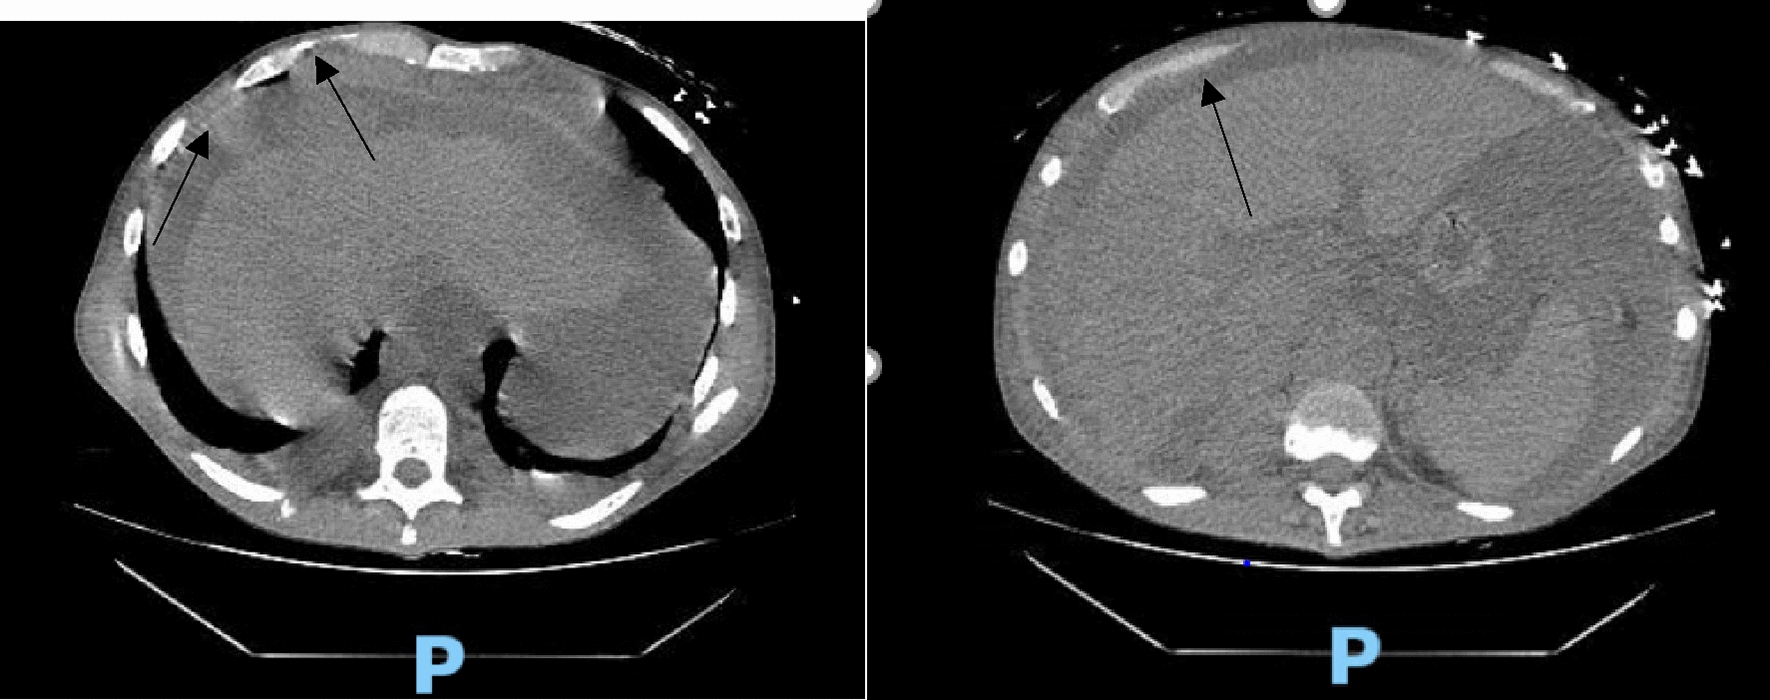

Hematology workup revealed mild leukocytosis (10.94 K/uL), normocytic anemia (hemoglobin 7.3 g/dL, mean corpuscular volume 94.4fL), and thrombocytosis (platelet count 901,000). Comprehensive metabolic panel was consistent with acute kidney injury (AKI) (creatinine 3 mg/dL, blood urea nitrogen 45 mg/dL—baseline unknown), tumor lysis syndrome (potassium 6.3 mmol/L, uric acid 21.7 mg/dL, phosphorus 5.6 mg/dL, and calcium 8 mg/dL). hyponatremia at 127 mmol/L, high anion gap metabolic acidosis (bicarbonate level 6, pH 7.23 on VBG, lactate 11.5), lactate dehydrogenase > 25,000 units/L, and elevated transaminases in a mixed pattern. Chest x-ray showed an ill-defined erosive mass of the left 4th to 5th lateral ribs, a thyroid mass, and trace pleural effusions (Fig. 1). Computerized tomography (CT) chest, abdomen, and pelvis had several significant findings pointing towards widespread malignancy. It showed a left supra-clavicular nodal mass measuring 5.4 × 4 × 3.6 cm, diffusely heterogeneous liver possibly reflecting metastatic disease, nodular soft tissue densities along with the hepatic capsule suspicious for hepatic capsular implants, large volume abdominopelvic ascites with extensive peritoneal soft tissue thickening/omental caking compatible with peritoneal carcinomatosis, mass-like thickening of the rectum, numerous lytic lesions involving the bilateral scapula, multiple ribs, bilateral proximal humerus, numerous vertebral bodies, pelvic bones, and proximal femur (Fig. 2). CT Head showed numerous diffuse lytic calvarial lesions concerning metastatic disease, but no mass effect was seen (Fig. 3).

Fig. 2.

CT abdomen and chest showing heterogeneous liver, possible hepatic capsular implants, large volume ascites involving abdomen and pelvis and omental caking